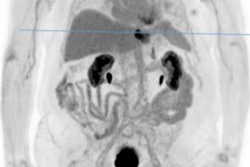

Traditional PET systems have limited range and sensitivity, and high dose exposure. FOV = field-of-view. All images courtesy of Prof. Thomas Beyer, PhD, MBA.Traditionally, PET imaging systems provide an axial field-of-view coverage of about 15-25 cm, sufficient to picture a single organ such as the brain or the heart. Whole-body scans using step-and-shoot, multibed positions, or continuous table motion, and applied in the majority of oncology indications, take 10 to 20 minutes. The exposure associated with the standard injection of FDG for a whole-body scan is about 7 mSv, which is around twice the annual background exposure. Furthermore, lesions smaller than 4 mm to 6 mm are difficult to detect. Importantly, traditional PET performance is relatively poor for late-time-point imaging, essential for antibody-labeled imaging for immune response assessment, Beyer noted.

Extended field-of-view systems increase sensitivity 40-fold for same injected activity.The latter is important because the longer the uptake time, the better benign from malignant disease and even low-grade from high-grade tissues can be differentiated in a multitude of tumors. Such late-time-point imaging can now be explored with the new extended axial field-of-view imaging PET systems that have entered the market, he noted.